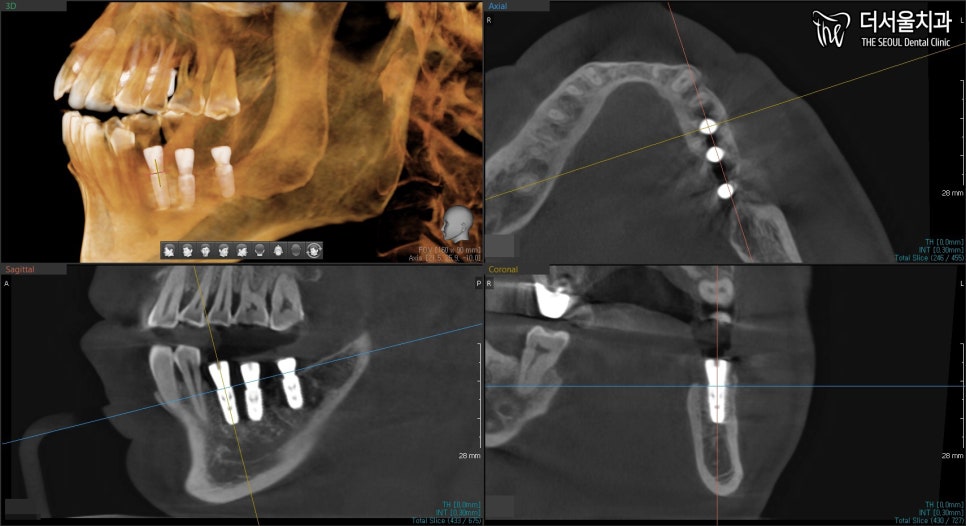

4. 과정

현충일 공휴일 정상진료

짜놓은 계획에 맞춰

픽스처를 심어줬습니다.

잇몸에 굳이 묻어둘 필요없이

‘힐링 어버트먼트’를 연결할 정도로

뼈 상태는 좋았습니다.

다만 이물질이나 음식물이 들어가게 될 경우,

안 좋은 결과를 줄 수 있기에

힐링 어버트먼트를 연결시켜 닫아줍니다.

엑스레이로 확인했을지라도

3D CT를 촬영하여 한번 더 체크해줍니다.

원하는 위치에 잘 심어졌네요 ^^

이제 서현역 치과는 뼈와 잘 붙길 기다려줍니다.